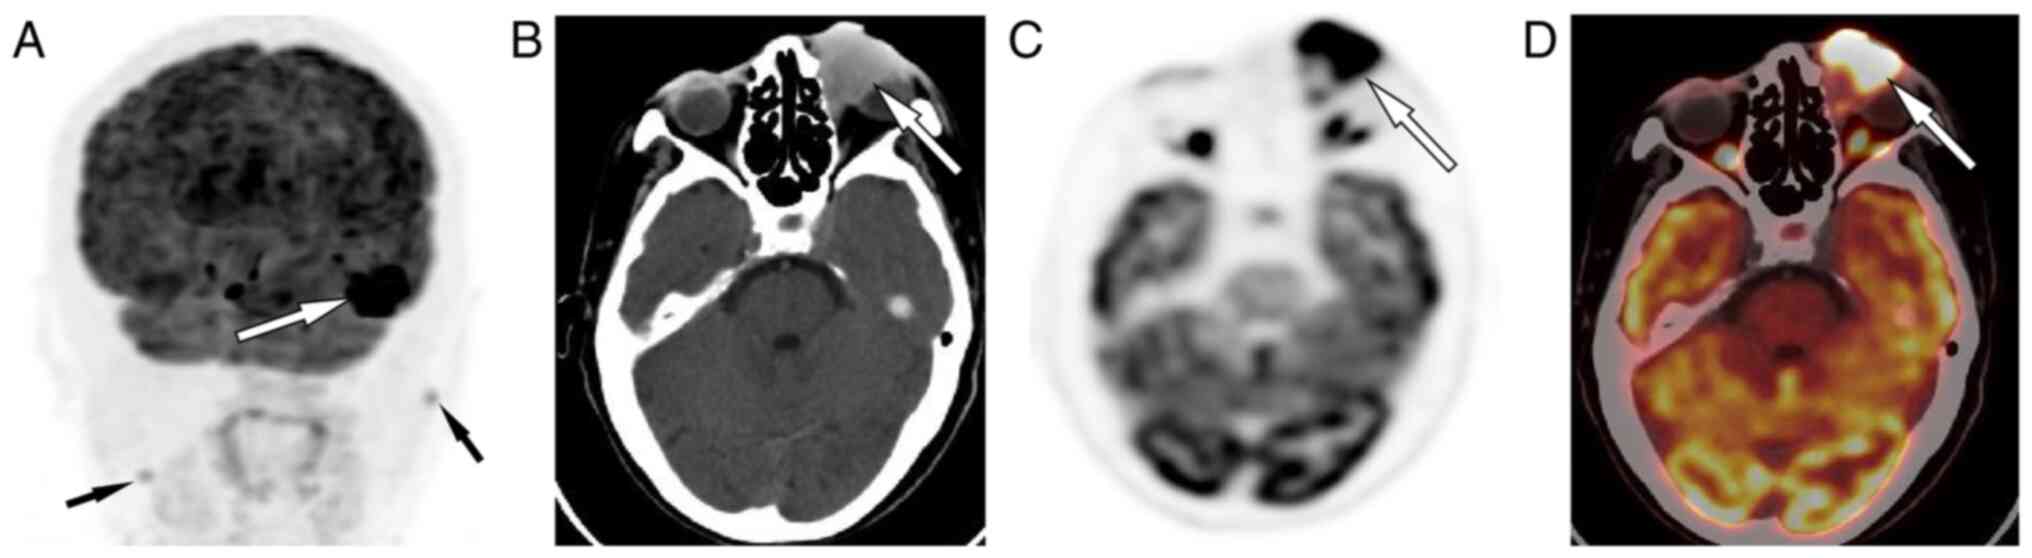

Figure 2.

(A) The maximum intensity projection map showed a lesion with intense 18F-FDG uptake in the left ocular region (white arrow). Moreover, additional 18F-FDG nodules with mild uptake were apparent bilaterally in the neck (black arrows), which were later pathologically confirmed to be inflammatory. (B) Axial CT showed the shadowing of the left ocular region as a homogeneous slightly hyperdense mass (white arrow). (C) Axial PET and (D) PET/CT fusion showed strong uptake of 18F-FDG in this lesion, with a maximum standardized uptake value of 12.8 (arrows). 18F-FDG, fluorine-18-fluorodeoxyglucose positron emission tomography; CT, computed tomography; PET, positron emission tomography.